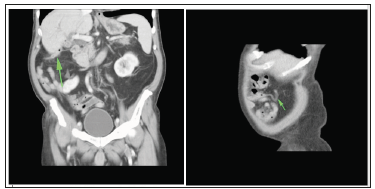

Differential diagnostics is usually performed with choledocholithiasis, cholangiocarcinoma, sclerosing cholangitis, malignant tumor of the gallbladder, pancreas, chronic pancreatitis. Established more accurate clinical and anamnestic characteristics of biliary tract fistulas: gallstone disease in history, weight loss, jaundice, recurrent chills, bouts of pain up to three to four times a year, discomfort in the right hypochondrium [3,4]. The peculiarity of the clinical course of biliodigestive fistulas is intermittent symptom of severe cholangitis due to the reflux of intestinal contents in the biliary system, as well as loss of body weight, signs of dyspepsy, and abundant liquid stool. Given the prevalence of gallstones and the danger of this, although rare, but it’s serious complication, such as the formation of biliodigestive fistula, we give the following clinical observation (Figure 1).

Figure 1:CT scan: Gallbladder-Appendicular Fistula

Multispiral computed tomography of the abdominal cavity and retroperitoneal space: signs of the gallstone disease, the gallbladder in a shriveled state, the walls are not clearly differentiated, inclusions suspicious for gas bubbles are visualized in the projection of the lumen. Choledocholithiasis. Biliary hypertension, initial signs of ductal hypertension with a block at the level of major duodenal papilla. Diffuse changes in the parenchyma of the liver and pancreas. In the area of the dome of the cecum, a worm-shaped process up to 16cm in size is visualized, which has a subhepatic arrangement and is intimately connected with the top of the gallbladder (fistula?). Incomplete doubling of the pyelocaliceal system of the right kidney.